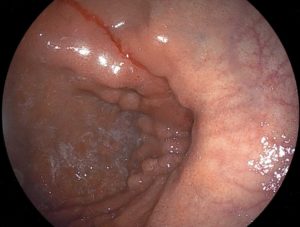

(1) 위내시경 검사

위축성 위염의 기본적인 진단은 위내시경 검사를 통해 이루어집니다. 내시경 검사 시 다음과 같은 특징적인 소견이 관찰됩니다:

- 위점막이 얇아진 상태

- 점막의 창백함

- 점막의 반짝거림

- 점막 아래 혈관이 투명하게 보임

- 위 주름의 감소

(2) 조직검사

내시경 검사 중 이상 소견이 발견되면 조직검사를 시행하여 위축성 위염의 심한 정도를 확인하고, 장상피화생이나 이형성증 같은 전암성 병변의 유무를 판단합니다.